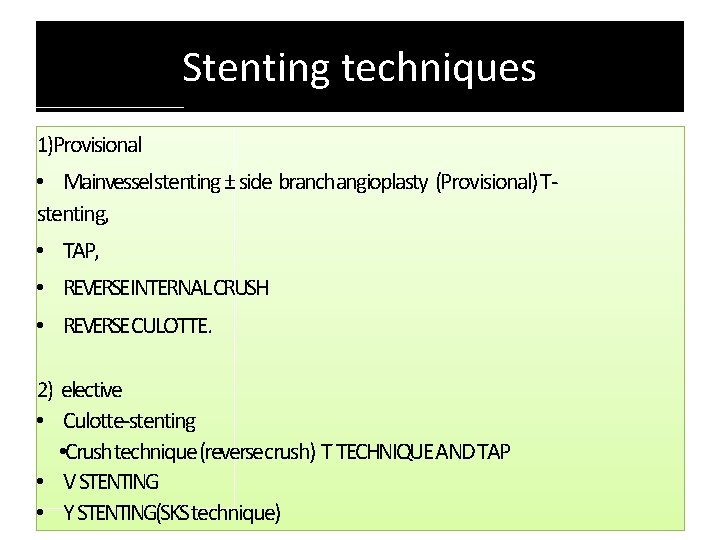

Stenting techniques 1)Provisional • Mainvessel stenting ± side branchangioplasty (Provisional) Tstenting, • TAP, • REVERSEINTERNAL CRUSH • REVERSECULOTTE. 2) elective • Culotte-stenting • Crush technique (reversecrush) T TECHNIQUE AND TAP • V STENTING • Y STENTING(SKS technique)